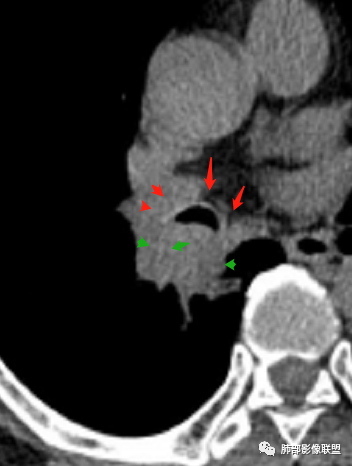

中老年男性,右肺下叶背段支气管内新生物,近端可见息肉样突起,远端沿分支支气管生长堵塞,肺门口病灶增强后明显强化,峰值达140hu,远端部分强化不明显考虑粘液栓,考虑典型类癌,鉴别鳞癌。

右肺叶中间段支气管见软组织影不完全阻塞及管腔变窄,向管腔外突破,向下叶背段浸润性生长,见指套及息肉样特点,不均匀明显强化,右肺下叶背段少许阻塞性炎症,肯定恶性肿瘤,小细胞Ca首先,支气管疾病谱恶性肿瘤:类癌,鳞癌,囊腺癌,粘液表皮样癌,与鳞癌,囊腺癌鉴别,支气管镜取材活检可以明确诊断。

软骨环的破坏与否很关键